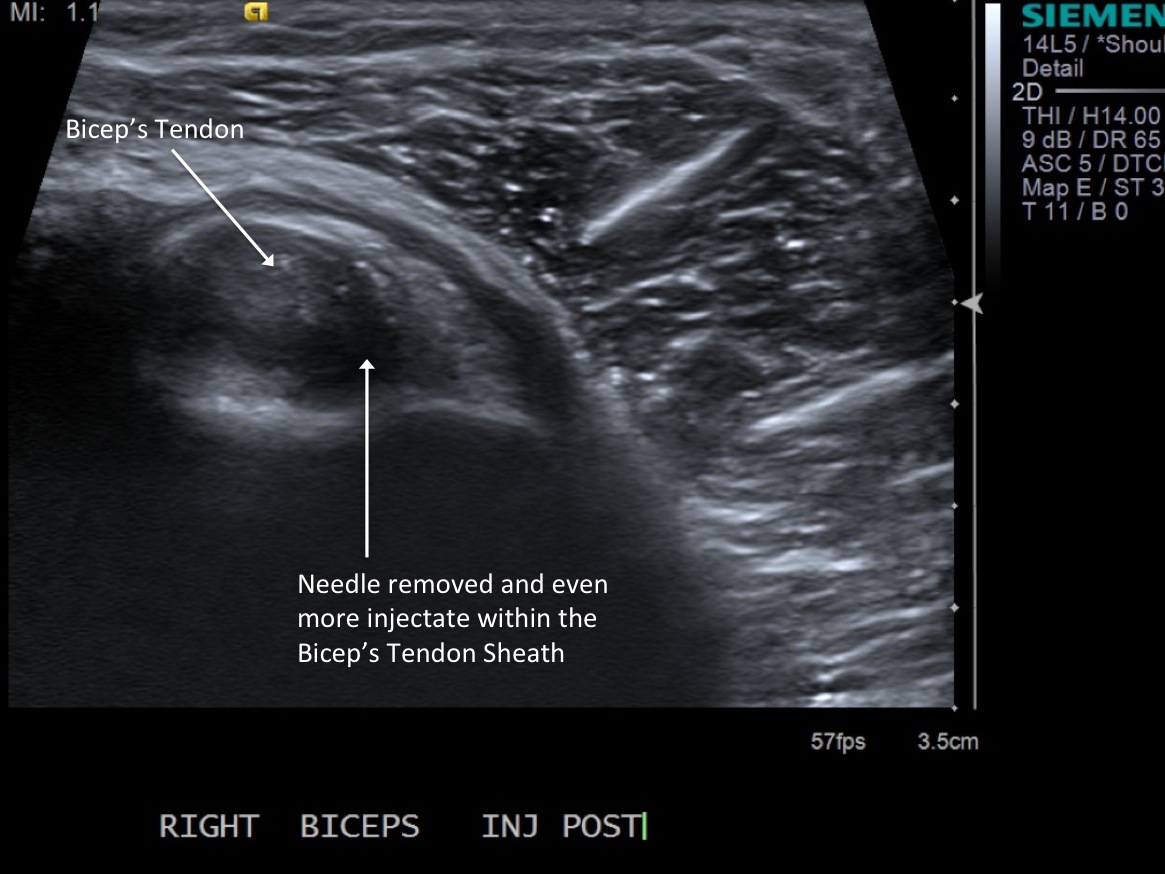

11. Test inject to see if easy flow with 1% lidocaine. If no resistance and see distention of the tendon sheath, exchange for 3cc syringe with injectable steroid and ropivacaine.

• descriptiondescription

12. Scan sheath to demonstrate distention.